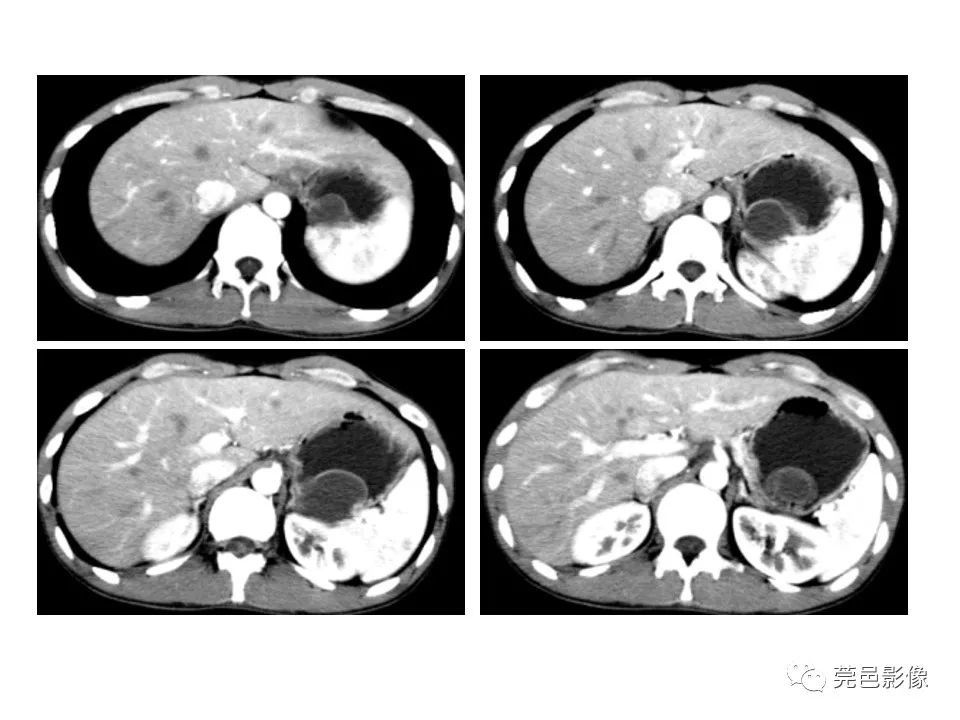

畸形|胃重复畸形CT诊断与鉴别诊断

【 畸形|胃重复畸形CT诊断与鉴别诊断】